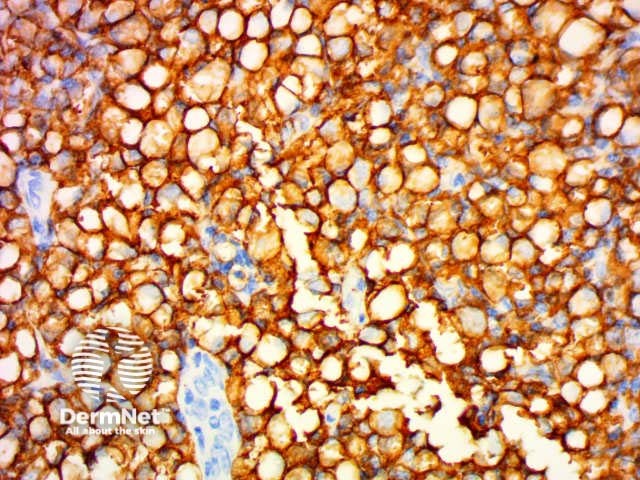

CD30 |

Can be used in the diagnosis of Hodgkin lymphoma and anaplastic lymphomas. Large cells: Golgi apparatus and membranous staining |

CD30